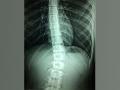

Health :Radiofrequency spinal cord stimulation shows improved longer-lasting pain relief: Study

According to a new study, chronic pain spinal cord stimulation (SCS) uses an implanted device to supply a small amount of electricity directly to the spinal cord, altering or blocking nerve activity and minimizing the sensation of pain reaching the b ...